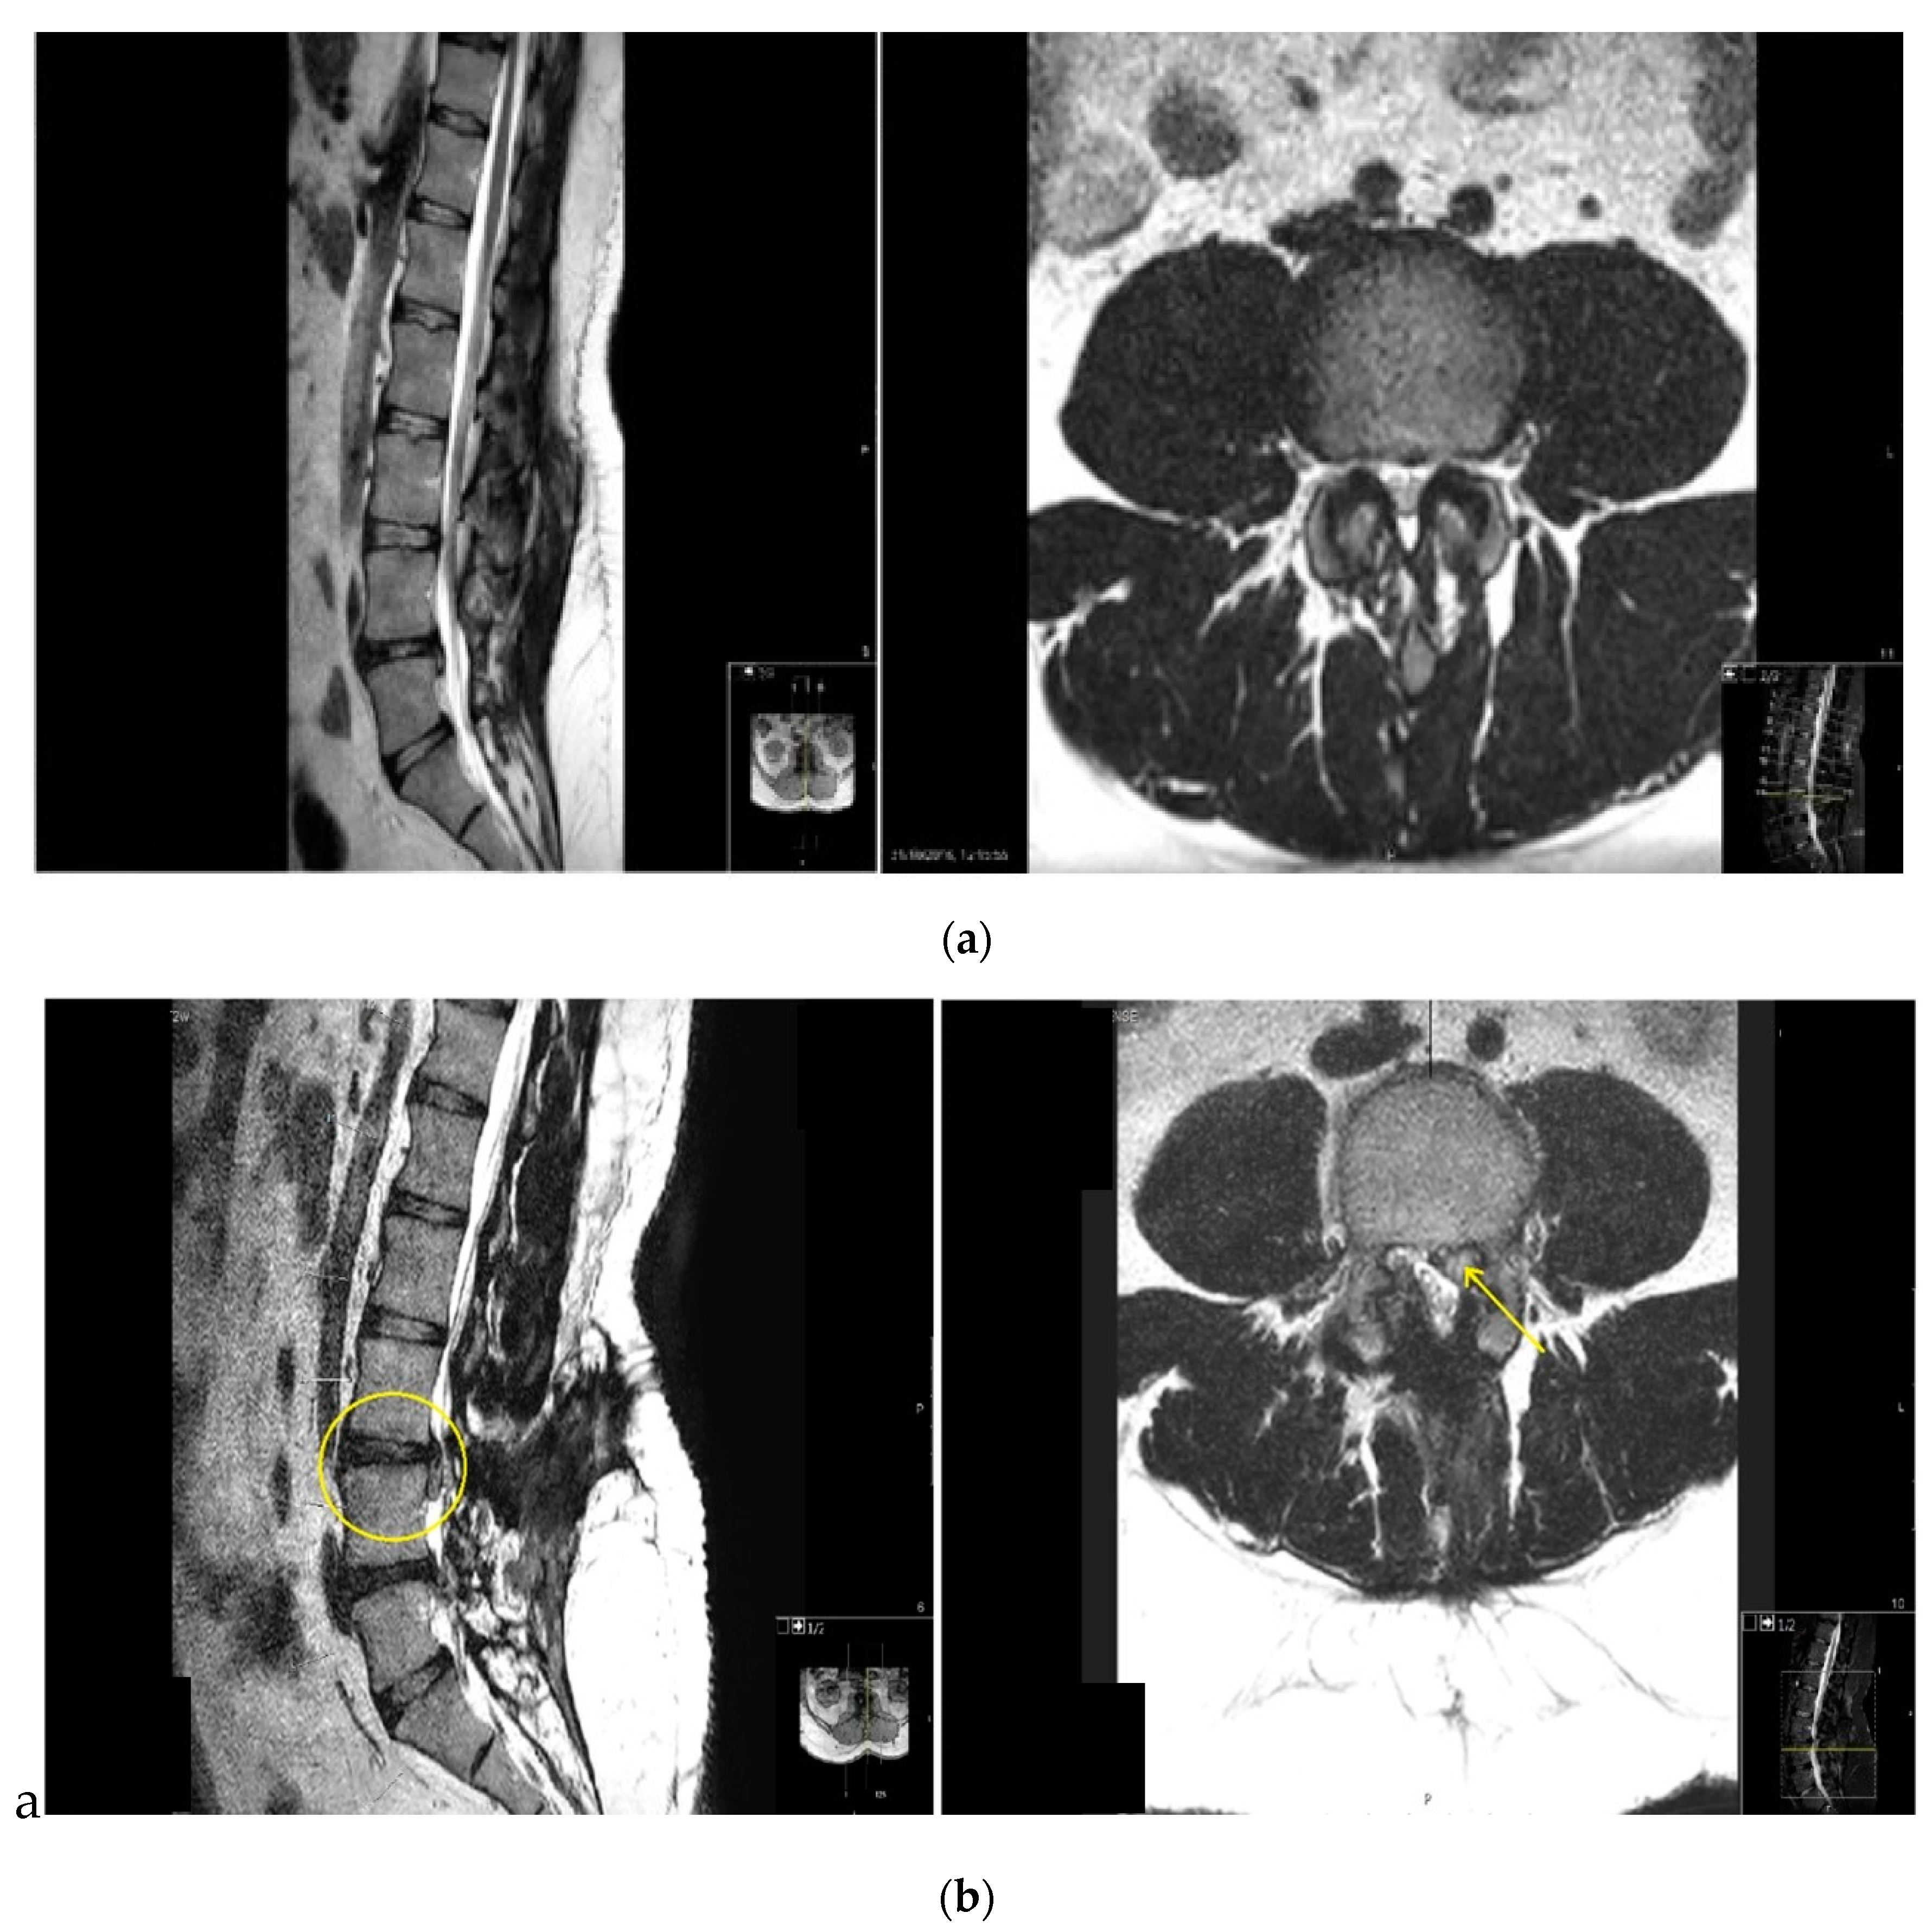

Of the 21 postoperative disc herniation (Figure 1), 6 underwent further discectomy surgery in which the herniated disc was removed with resolution of radicular pain.

Figure 1. T2-MRI of lumbar spine (a) before index surgery (b) disc herniation after decompression.